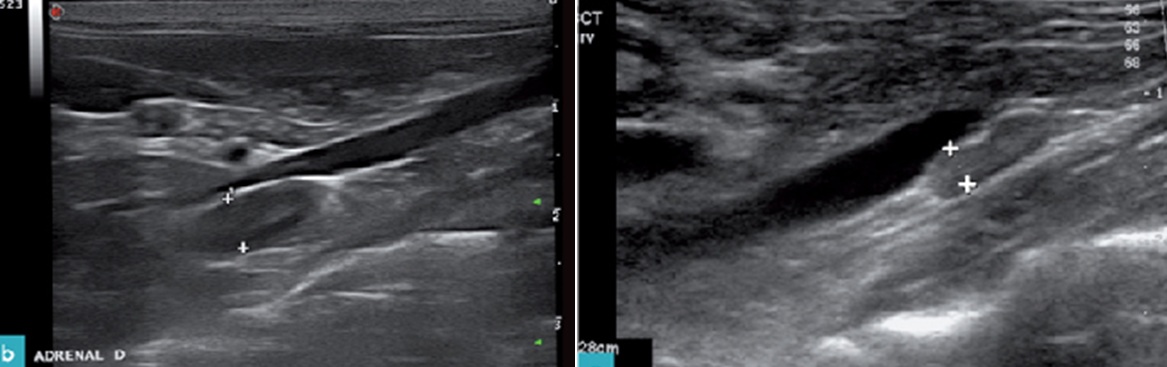

4. 실습을 통한 데일리벳 커뮤니티의 측정

실습을 통하여 데일리벳 커뮤니티의 부신을 관찰하고 측정한 그림입니다(그림 4).

데일리벳 커뮤니티에서는 좌측 부신은 대동맥에서 신장동맥보다는 전장간막동맥을 이정표로 하면 쉽게 찾으며, 우측 부신은 우측 신장의 약간 앞쪽 위치의 CVC에서 찾으면 쉽게 찾게 됩니다(7).